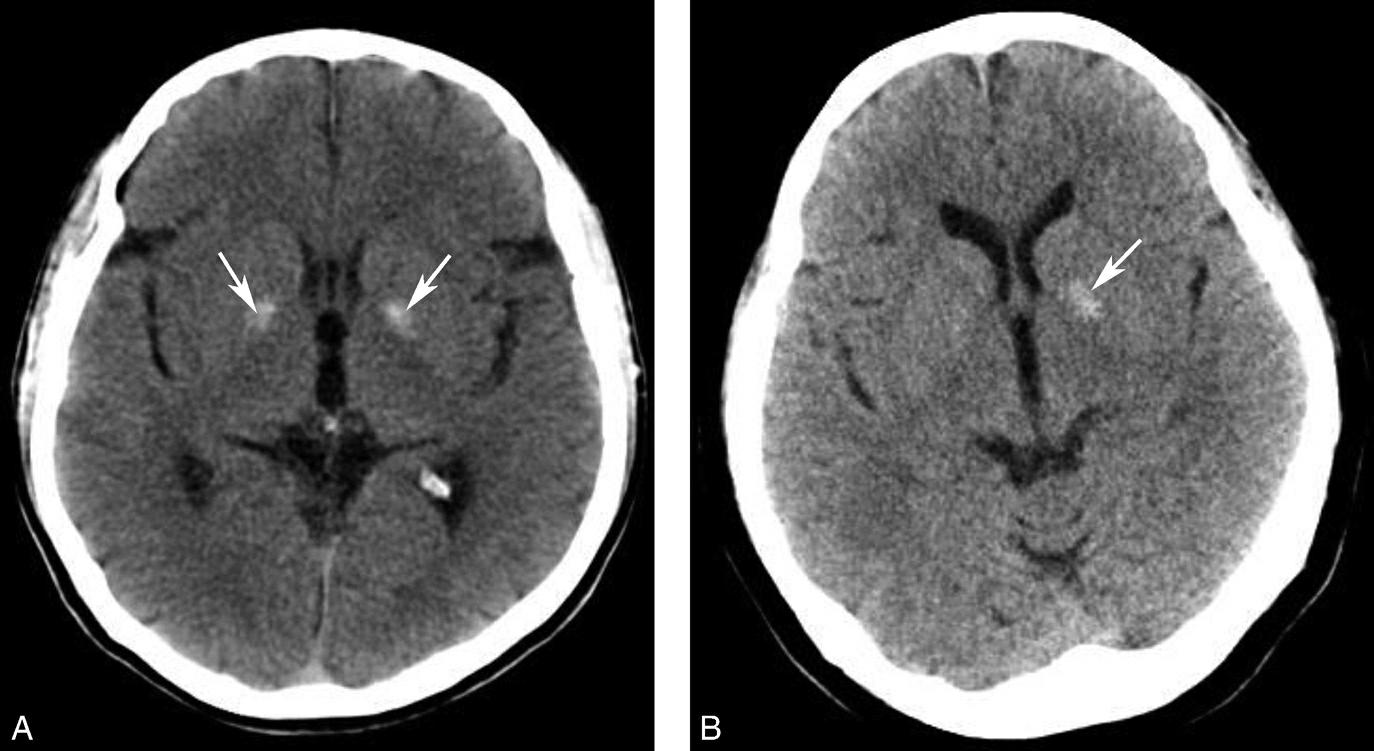

松果体、苍白球在成人期常出现钙化,属生理性钙化,一般无病理意义。需注意勿误诊为出血灶,尤其是单侧苍白球钙化时(图1-2-28)。

图1-2-28 苍白球生理性钙化

A.双侧苍白球对称性钙化,呈高密度影(箭);B.左侧苍白球钙化(箭),右侧苍白球钙化不明显